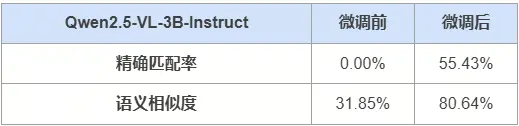

在共451題的測試集中,模型Qwen2.5-VL-3B-Instruct微調前後的精確匹配率和語義相似度如下所示:

- 示例

針對如下影像,微調前後的輸出